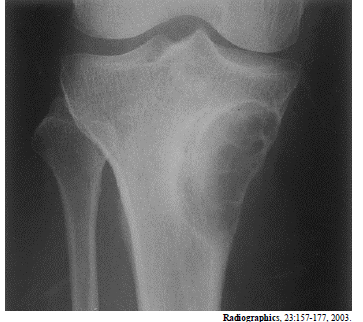

A radiografia acima é de um paciente do sexo masculino, com 25 anos de idade, com queixa de dores no joelho. Considerando essa imagem, é correto afirmar que

fibroma não ossificante é um diagnóstico diferencial adequado.

a lesão é do tipo metafisária.

a lesão tem aspecto de benignidade.

a lesão é predominantemente blástica.

o diagnóstico mais provável é de tumor de células gigantes.

a lesão situa-se na medular.